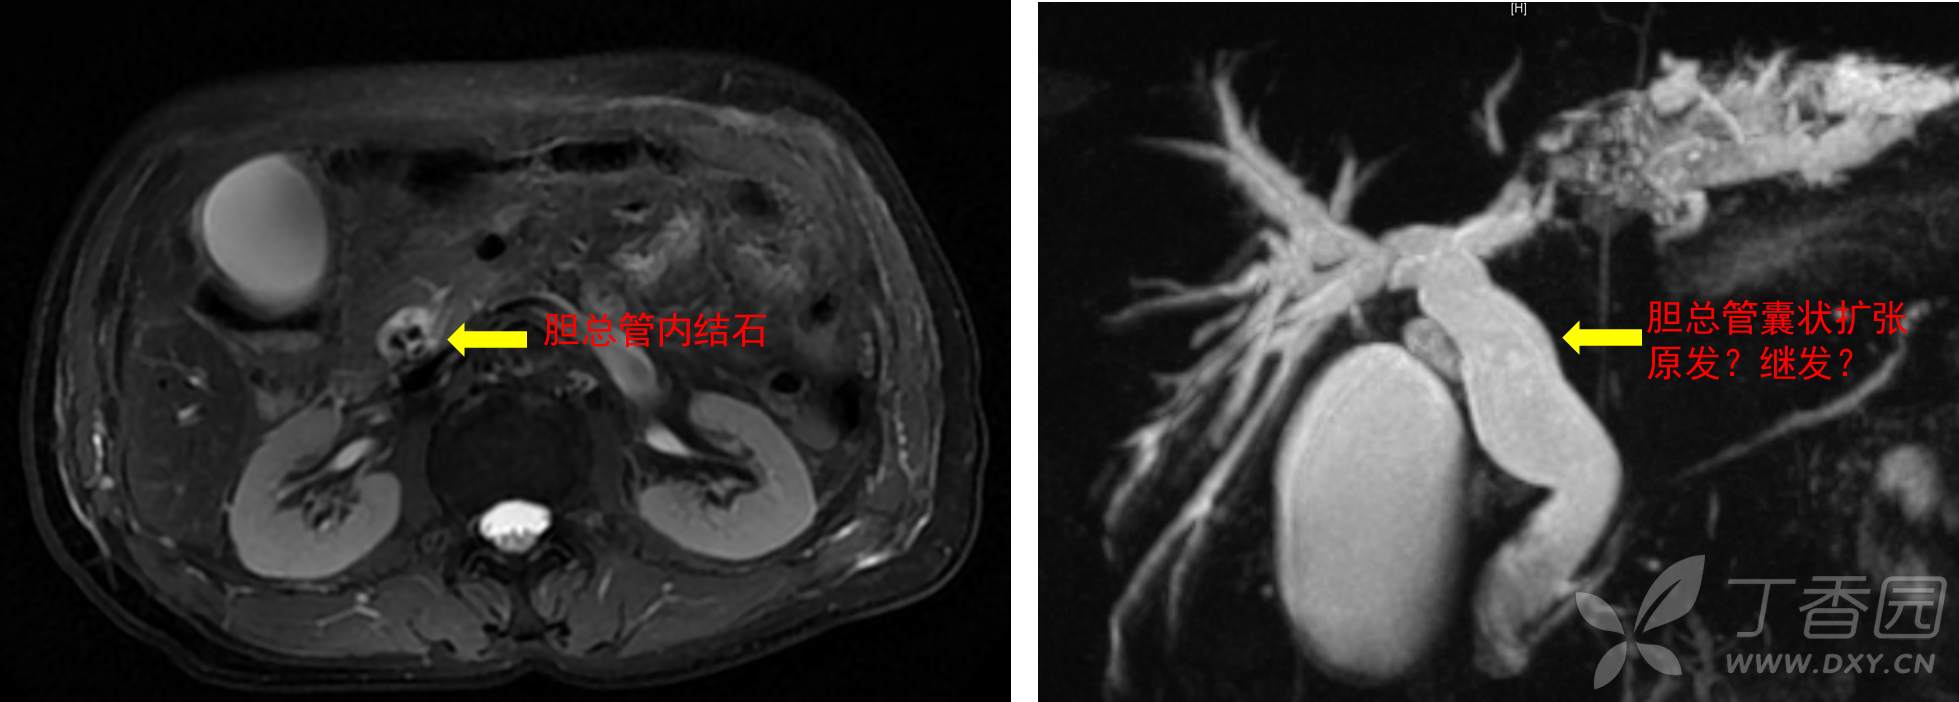

65岁男性,腹痛黄疸发热来院就诊,典型胆管炎表现,影像学检查发现肝内外胆管结石,如图:

术前诊断:1、梗阻性黄疸并胆管炎;2、肝内外胆管结石;3、左肝萎缩不除外癌变;4、先天性胆管总管囊状扩张;4、乙肝。